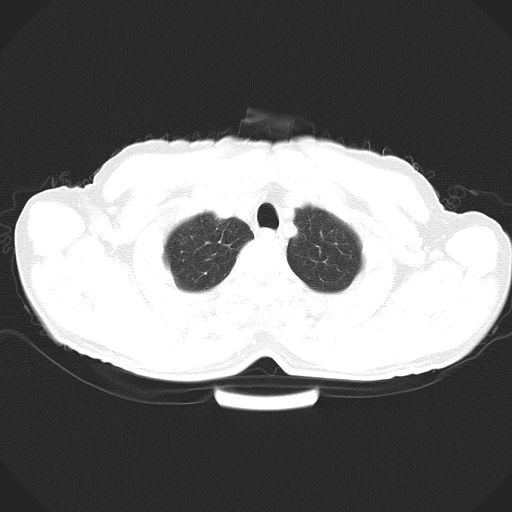

以下是引用心路寻觅在2010-3-1 10:23:00的发言:[br]1、考虑左肺上叶周围型肺癌[br]2、右上肺陈旧性病灶。[br][br][本贴已被 心路寻觅 于 2010-3-1 10:40:18 修改过]

以下是引用shuiyuan在2010-3-1 10:45:00的发言:[br]考虑左肺上叶中心型肺癌伴阻塞型炎症,邻近胸膜受侵。